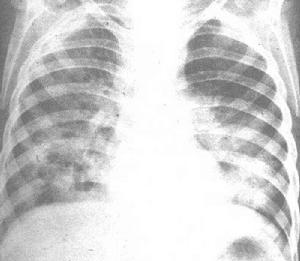

(3)急性肺部感染:是本病最常見的形式。表現為原發性或血源播散性肺炎。起病突然,畏寒或寒戰,繼而發熱,全身肌肉痛,頭痛、咳嗽、胸痛、呼吸急促,肺部可聽到囉音 X線檢查肺部實變,有的可發生薄壁空洞 當體溫下降時空洞可持久存在,酷似肺結核的X線表現。某些患者可相繼發生進行性肺內播散或血源性播散 發展為敗血症。

(4)急性敗血症性感染:起病突然,寒戰、高熱 頭部、軀幹和四肢皮膚發生小膿皰。如合併肺炎常伴有嚴重呼吸困難,劇烈頭痛,咳嗽及胸痛。肺部出現濕性囉音及胸膜摩擦音。X線檢查常顯示遍及全肺的、直徑4~10mm不規則的結節狀陰影,繼而結節擴大融合形成空洞。患者可伴發關節炎或腦膜炎。肝脾大。預後差,病情發展迅速,常不及治療而死亡。

X線檢查顯示肺炎 肺化膿症及膿胸。